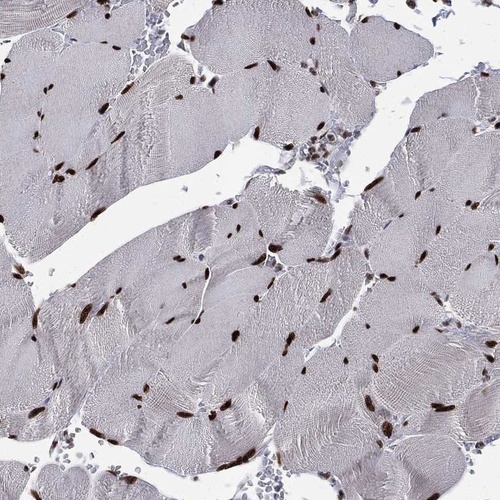

Immunohistochemical staining of human skeletal muscle shows strong nuclear positivity in myocytes.